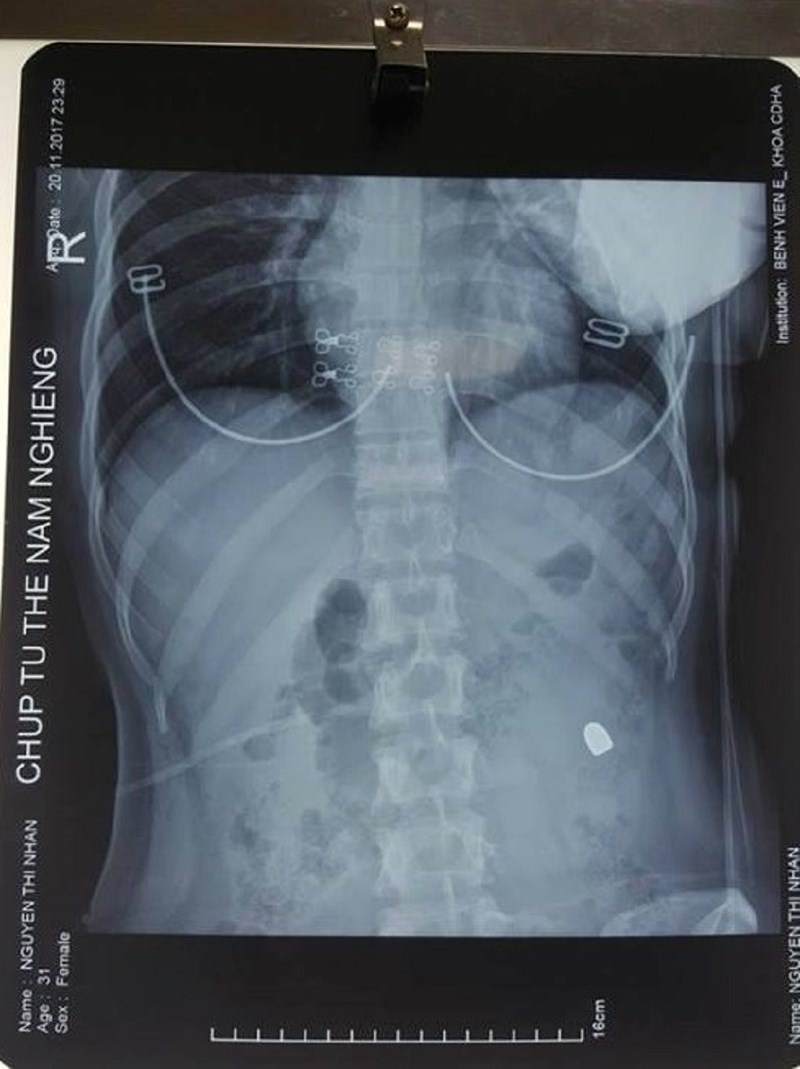

Viên đạn xuyên thủng vùng bụng của nạn nhân. |

Kết quả chụp X-quang cho thấy một đầu đạn nằm tại mạn sườn trái của bệnh nhân, cô được đưa lên phòng mổ.

Phim chụp X-quang cho thấy viên đạn nằm sâu trong bụng nạn nhân. |